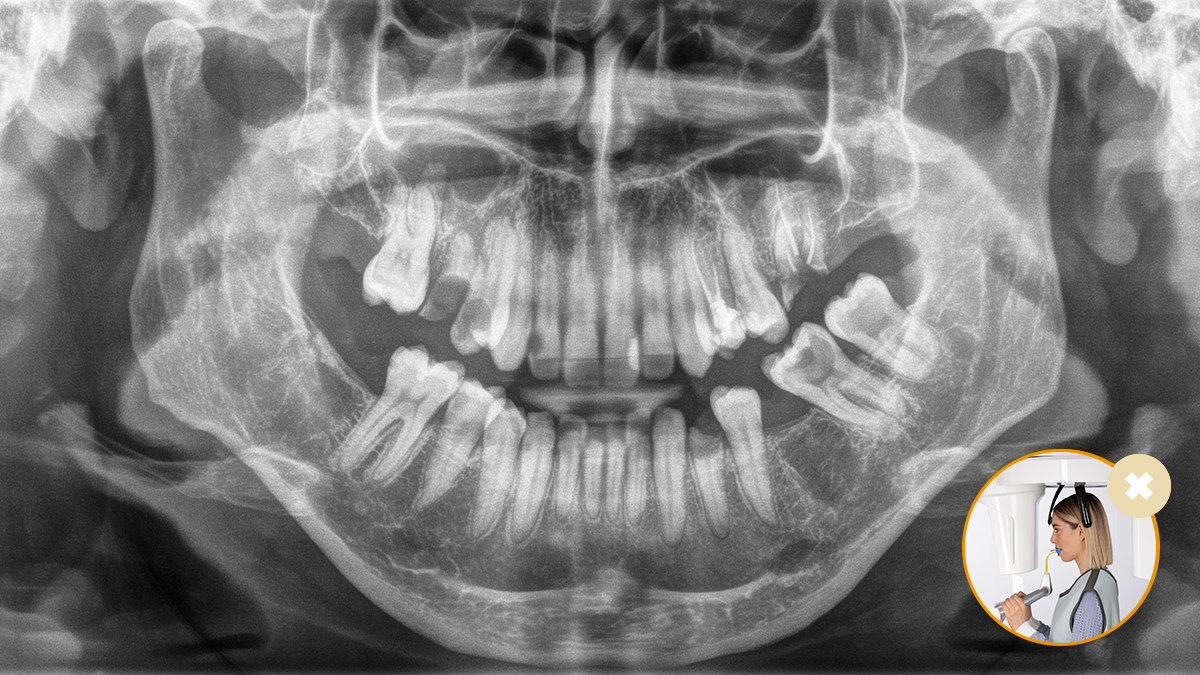

El posicionamiento correcto del paciente permite obtener imágenes de alta calidad que respaldan un diagnóstico preciso y facilitan y mejoran la experiencia del paciente.

Este es nuestro concepto de 10 puntos para facilitar el posicionamiento del paciente y la obtención de imágenes radiológicas. Se trata principalmente de dos cosas: alta calidad de imagen y comodidad para el paciente y el asistente.

El resultado: Escaneos precisos gracias al bloque de mordida oclusal